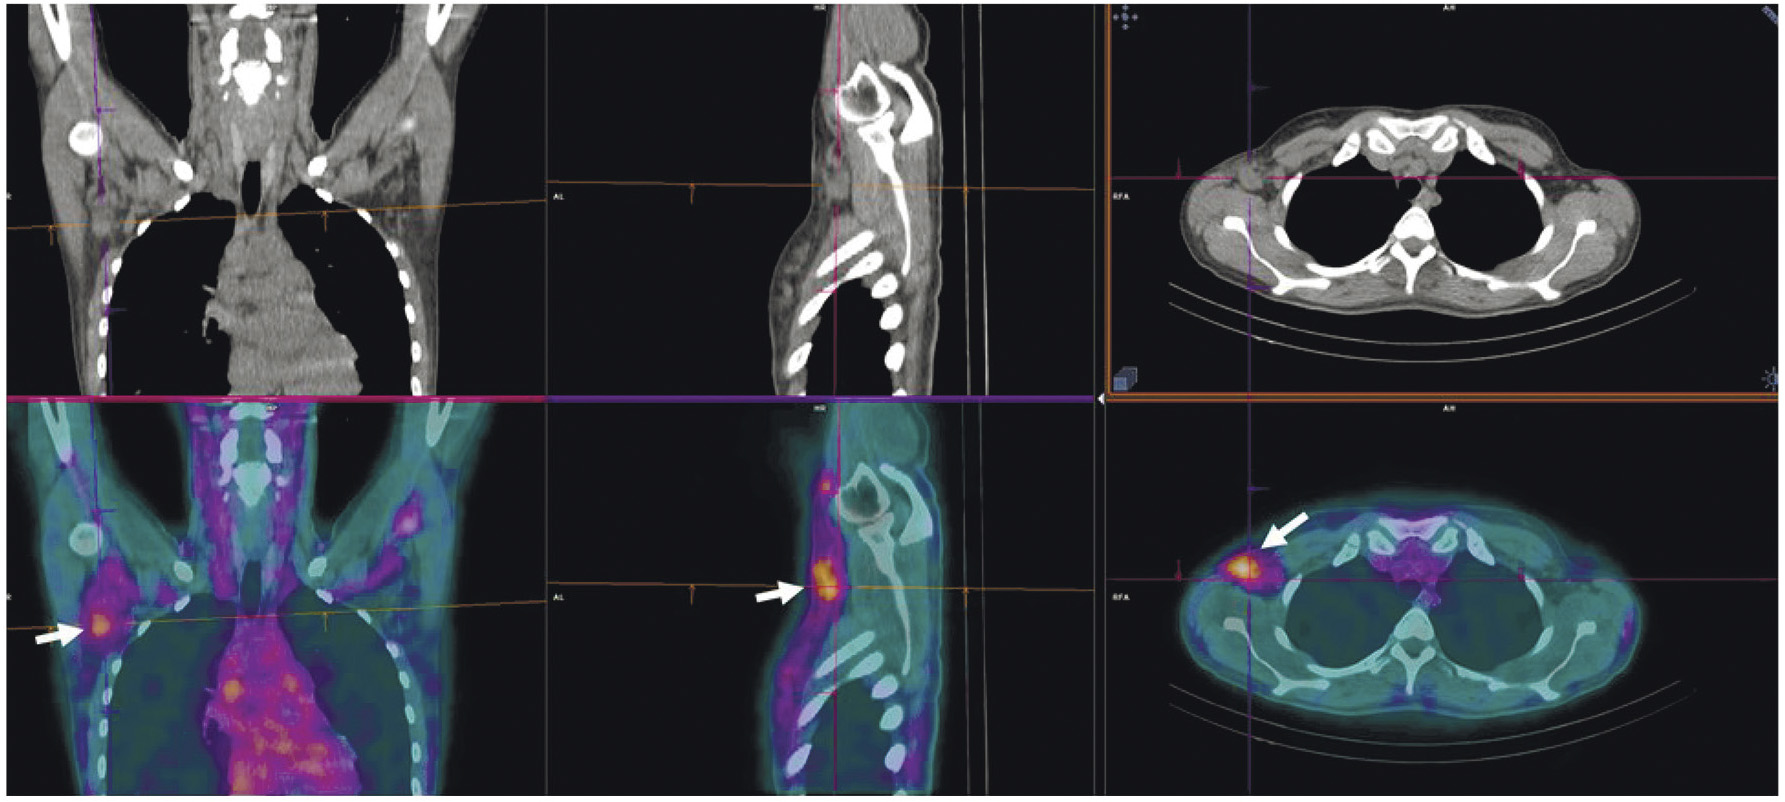

В НИИ онкологии Томского НИМЦ завершены первые фазы клинических исследований нескольких меченных технецием-99м каркасных белков (DARPin, ADAPT, Affibody), обладающих высокой аффинностью к рецептору эпидермального фактора роста второго типа (HER2/neu). Все препараты показали хорошую эффективность определения гиперэкспрессии рецептора HER2/neu при раке молочной железы и стадировании заболевания (рис. 1) [10, 11]. Кроме того, установлена возможность проведения ОФЭКТ/КТ с препаратами на базе скаффолдов для оценки эффекта терапии (рис. 2). Помимо основы РФЛП для диагностики злокачественных новообразований, каркасные белки могут служить вектором доставки при создании таргетных соединений для лечения злокачественных новообразований с гиперэкспрессией рецептора HER2/neu [13].

Рис. 1. ПЭТ-изображение пациентки с HER2/neu-позитивным раком молочной железы, выполненное через 5 суток после введения 89Zr-транстузумаба (a), стрелками обозначены метастазы в печень и кости [12]; ОФЭКТ-изображение пациентки с HER2/neu-позитивным раком молочной железы через 2 ч после введения 99mTc-ADAPT6 (б), стрелками обозначены первичная опухоль, метастазы в лимфатические узлы, печень и кости

Рис. 2. ОФЭКТ/КТ-изображение пациентки с HER2/neu-позитивным раком правой молочной железы до начала лечения, выполненное через 2 ч после введения 99mTc-DARPIN-G3 (а), стрелками обозначены первичная опухоль (SUVmax = 3.1), метастазы в лимфатические узлы (SUVmax = 8.8) и кости; ОФЭКТ/КТ-изображение той же пациентки после двух курсов терапии транстузумабом через 2 ч после введения 99mTc-DARPIN-G3 (б), стрелками обозначена первичная опухоль (SUVmax = 0.55), метастазы не визуализируются